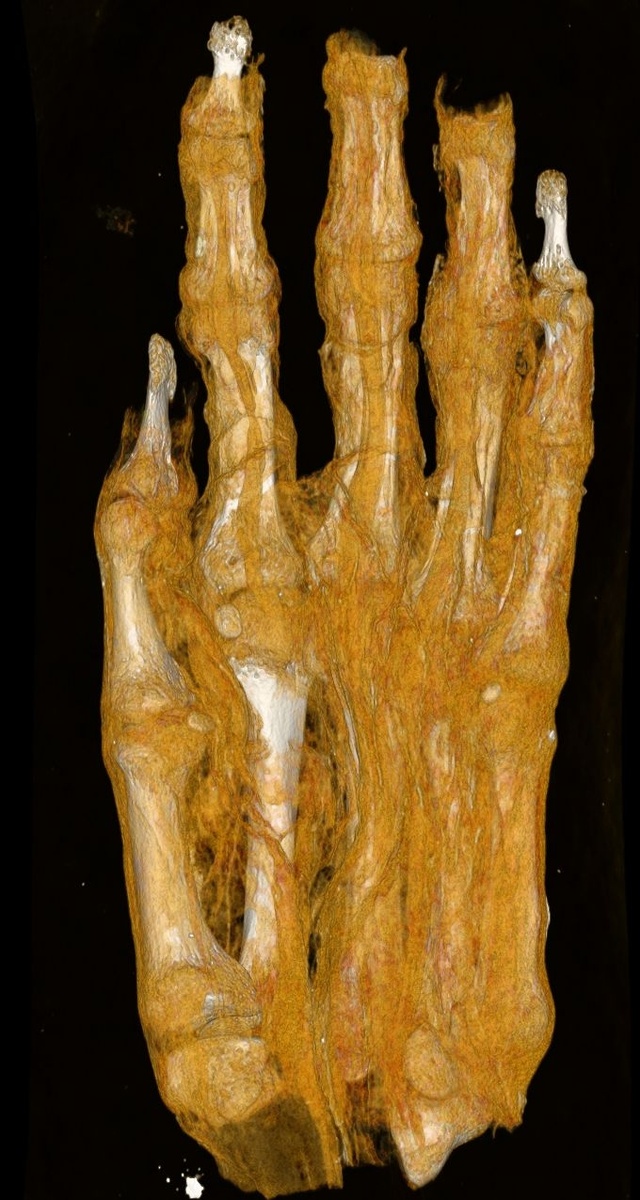

Компьютерную томографию мумифицированных голов проводили с целью установить пол и индивидуальный возраст этих людей, а в перспективе реконструировать их лица. Но интересовали ученых не только головы. Например, установлено, что обладатель левой ноги, хранившейся в музее, страдал остеопорозом. Правая нога, от другой мумии, как выяснилось, принадлежала молодому человеку.

Интереснее всего анализ артефакта, ранее неопределенно описанного как «мумифицированный сверток». Первоначально находку интерпретировали как человеческую голову, затем как мумию... птицы. Однако компьютерная томография показала, что на самом деле экспонат представляет собой ступню взрослого человека. К сожалению, к публикации не прилагается фотографии находки.